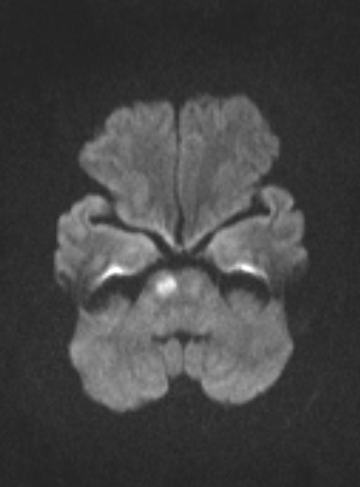

Hình ảnh Cộng hưởng từ sọ não (MRI) người phụ nữ bị ong đốt: Với xung khuếch tán Diffusion cho kết quả nhồi máu cầu não phải. (Ảnh: Bệnh viện Đa khoa tỉnh Phú Thọ).

Bước đầu bác sĩ nhận định, phản ứng qua trung gian miễn dịch của hệ thống đối với vết ong đốt gây ra co mạch và trạng thái tạo huyết khối kèm theo thiếu máu cục bộ dẫn đến đột quỵ. Bệnh nhân được tiến hành chụp Cộng hưởng từ sọ não ghi nhận nhồi máu cầu não phải.